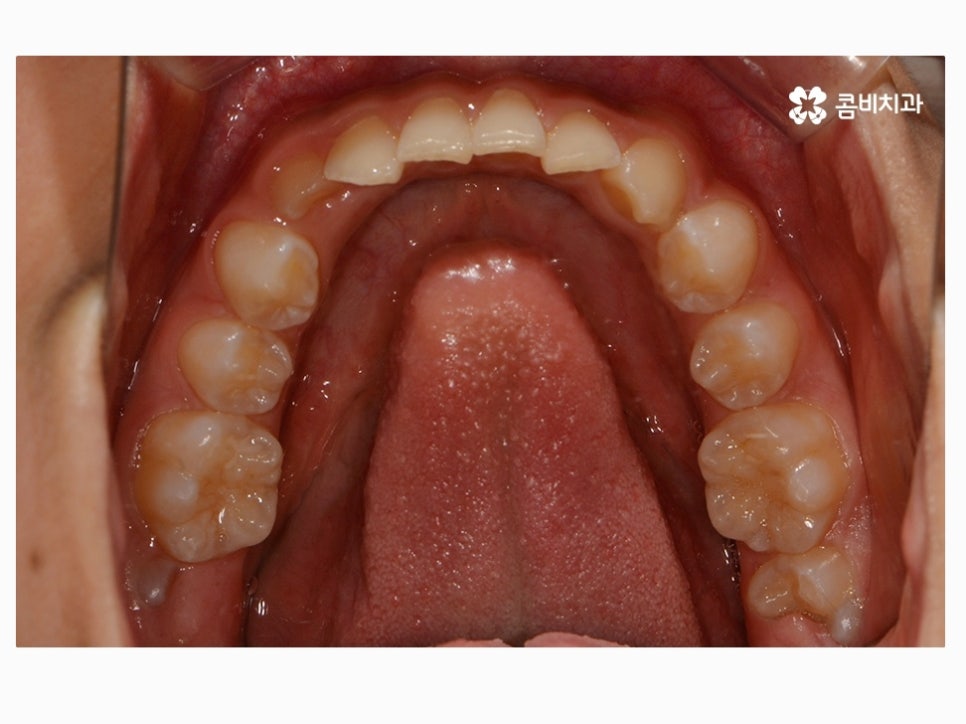

과개교합은 부정교합의 종류 중 하나라고 할 수 있으며

윗니가 아랫니를 정상보다 많이 덮고 있는 형태로 흔히 과개교합 혹은

피개교합으로도 불리고 있어요.

아직 성장이 진행되고 있는 나이에 치아교정을 하면 치아와 골격, 얼굴형 뿐 아니라

성장에 대한 예측을 함께 해야 하기 때문에 보다 세심한 진료와

경과를 자주 살펴보면서 치료가 안전하게 진행되는 것이 중요할 수 있는데요.